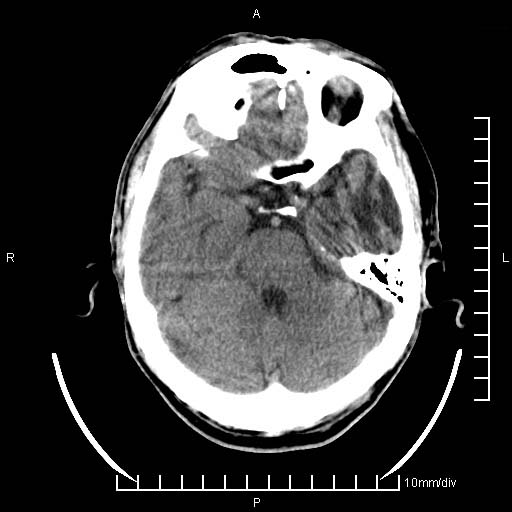

临床以双下肢浮肿,疼痛收治,无明显神经系统症状,既往无梗塞,出血病史。左颞叶见低密度灶,考虑什么?

考虑左侧颞叶脑软化灶。

无强化 无占位 软化灶吧

无强化、 无占位、局部脑沟增宽, 软化灶吧。